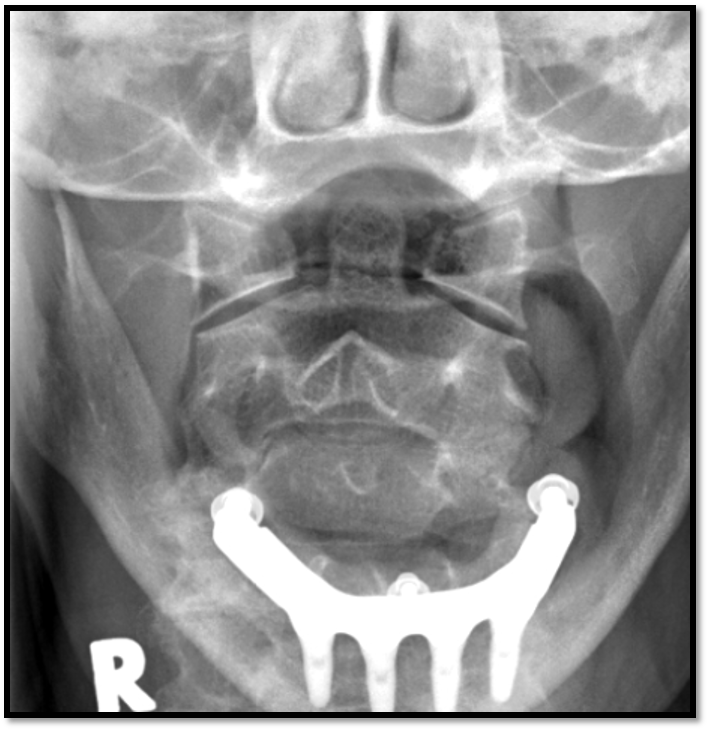

Odontoid Image Criteria

A

• equal distance between dens and lateral masses

• upper incisors aligned with base of skull

• must see lateral edges of C1 and C2

17

Q

• need to tuck chin

• nose is slightly rotated to the right